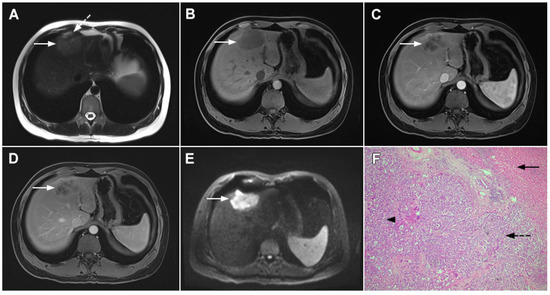

Target sign, consisting of diffusion restriction at the periphery of the lesion and low signal intensity in its central parts on high-b-value diffusion weighted imaging (DWI), could be considered to be a pathognomonic finding in mICC [16,17]. It can be attributed to the loose central fibrotic stroma with accompanying edema that is responsible for low signal intensity in DWI, while the periphery of the lesion is composed of densely packed viable tumor cells that cause diffusion restriction and dark rings on the apparent diffusion coefficient (ADC) map (Figure 3) [16].

Figure 3.

Mass-forming intrahepatic cholangiocarcinoma in the left liver lobe of a 76-year-old man. Axial T2-weighted FS image shows lobulated hetrogeneously hyperintense hepatic tumor (arrow) with perilesional biliary dilatation (A). Axial diffusion-weighted image (b = 800 s/mm2) shows target-like appearance (arrow) of the lesion that consists of a central darker area and a peripheral hyperintense area (B). Corresponding ADC map is shown on (C).